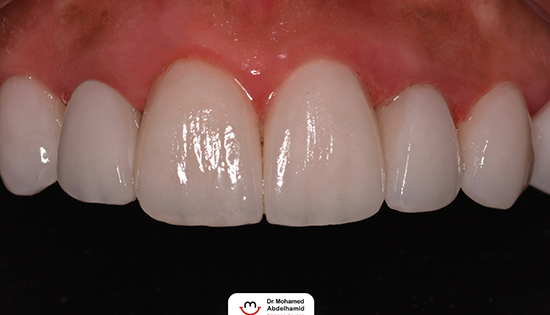

يلجأ الشخص إلى تحسين شكل أسنانه عن طريق فينير الأسنان أو ما يطلق عليه (عدسات الأسنان اللاصقة) وهي عبارة قشرة رقيقه يتم لصقها على السطح الخارجي للأسنان مصنوعة من مواد صلبة ذات معامل شفافيه مطابق للأسنان الطبيعيه   لعلاج مشكلة الاصفرار أو عدم التساوي والعديد من المشاكل الأخرى، حتى يحصل الشخص على ابتسامة رائعة تشبه ابتسامة نجوم هوليود.

• إظهار الأسنان بشكل أكثر جمالًا بعد تغطية كل عيوب الاسنان.

• يحتفظ الفينيرز بلونه وخصائصه لأعوام عديده.

• نقوم بتحضير الأسنان باستخدام الميكروسكوب لضمان اعلى قدر من الدقه في كل مراحل تنفيذ الڤينيرز.

• نعتمد في تصنيع الڤينيرز علي طاقم فني من امهر الفنيين في الوطن العربي ولهم خبره طويله جداً في تجميل اسنان العديد من المشاهير.